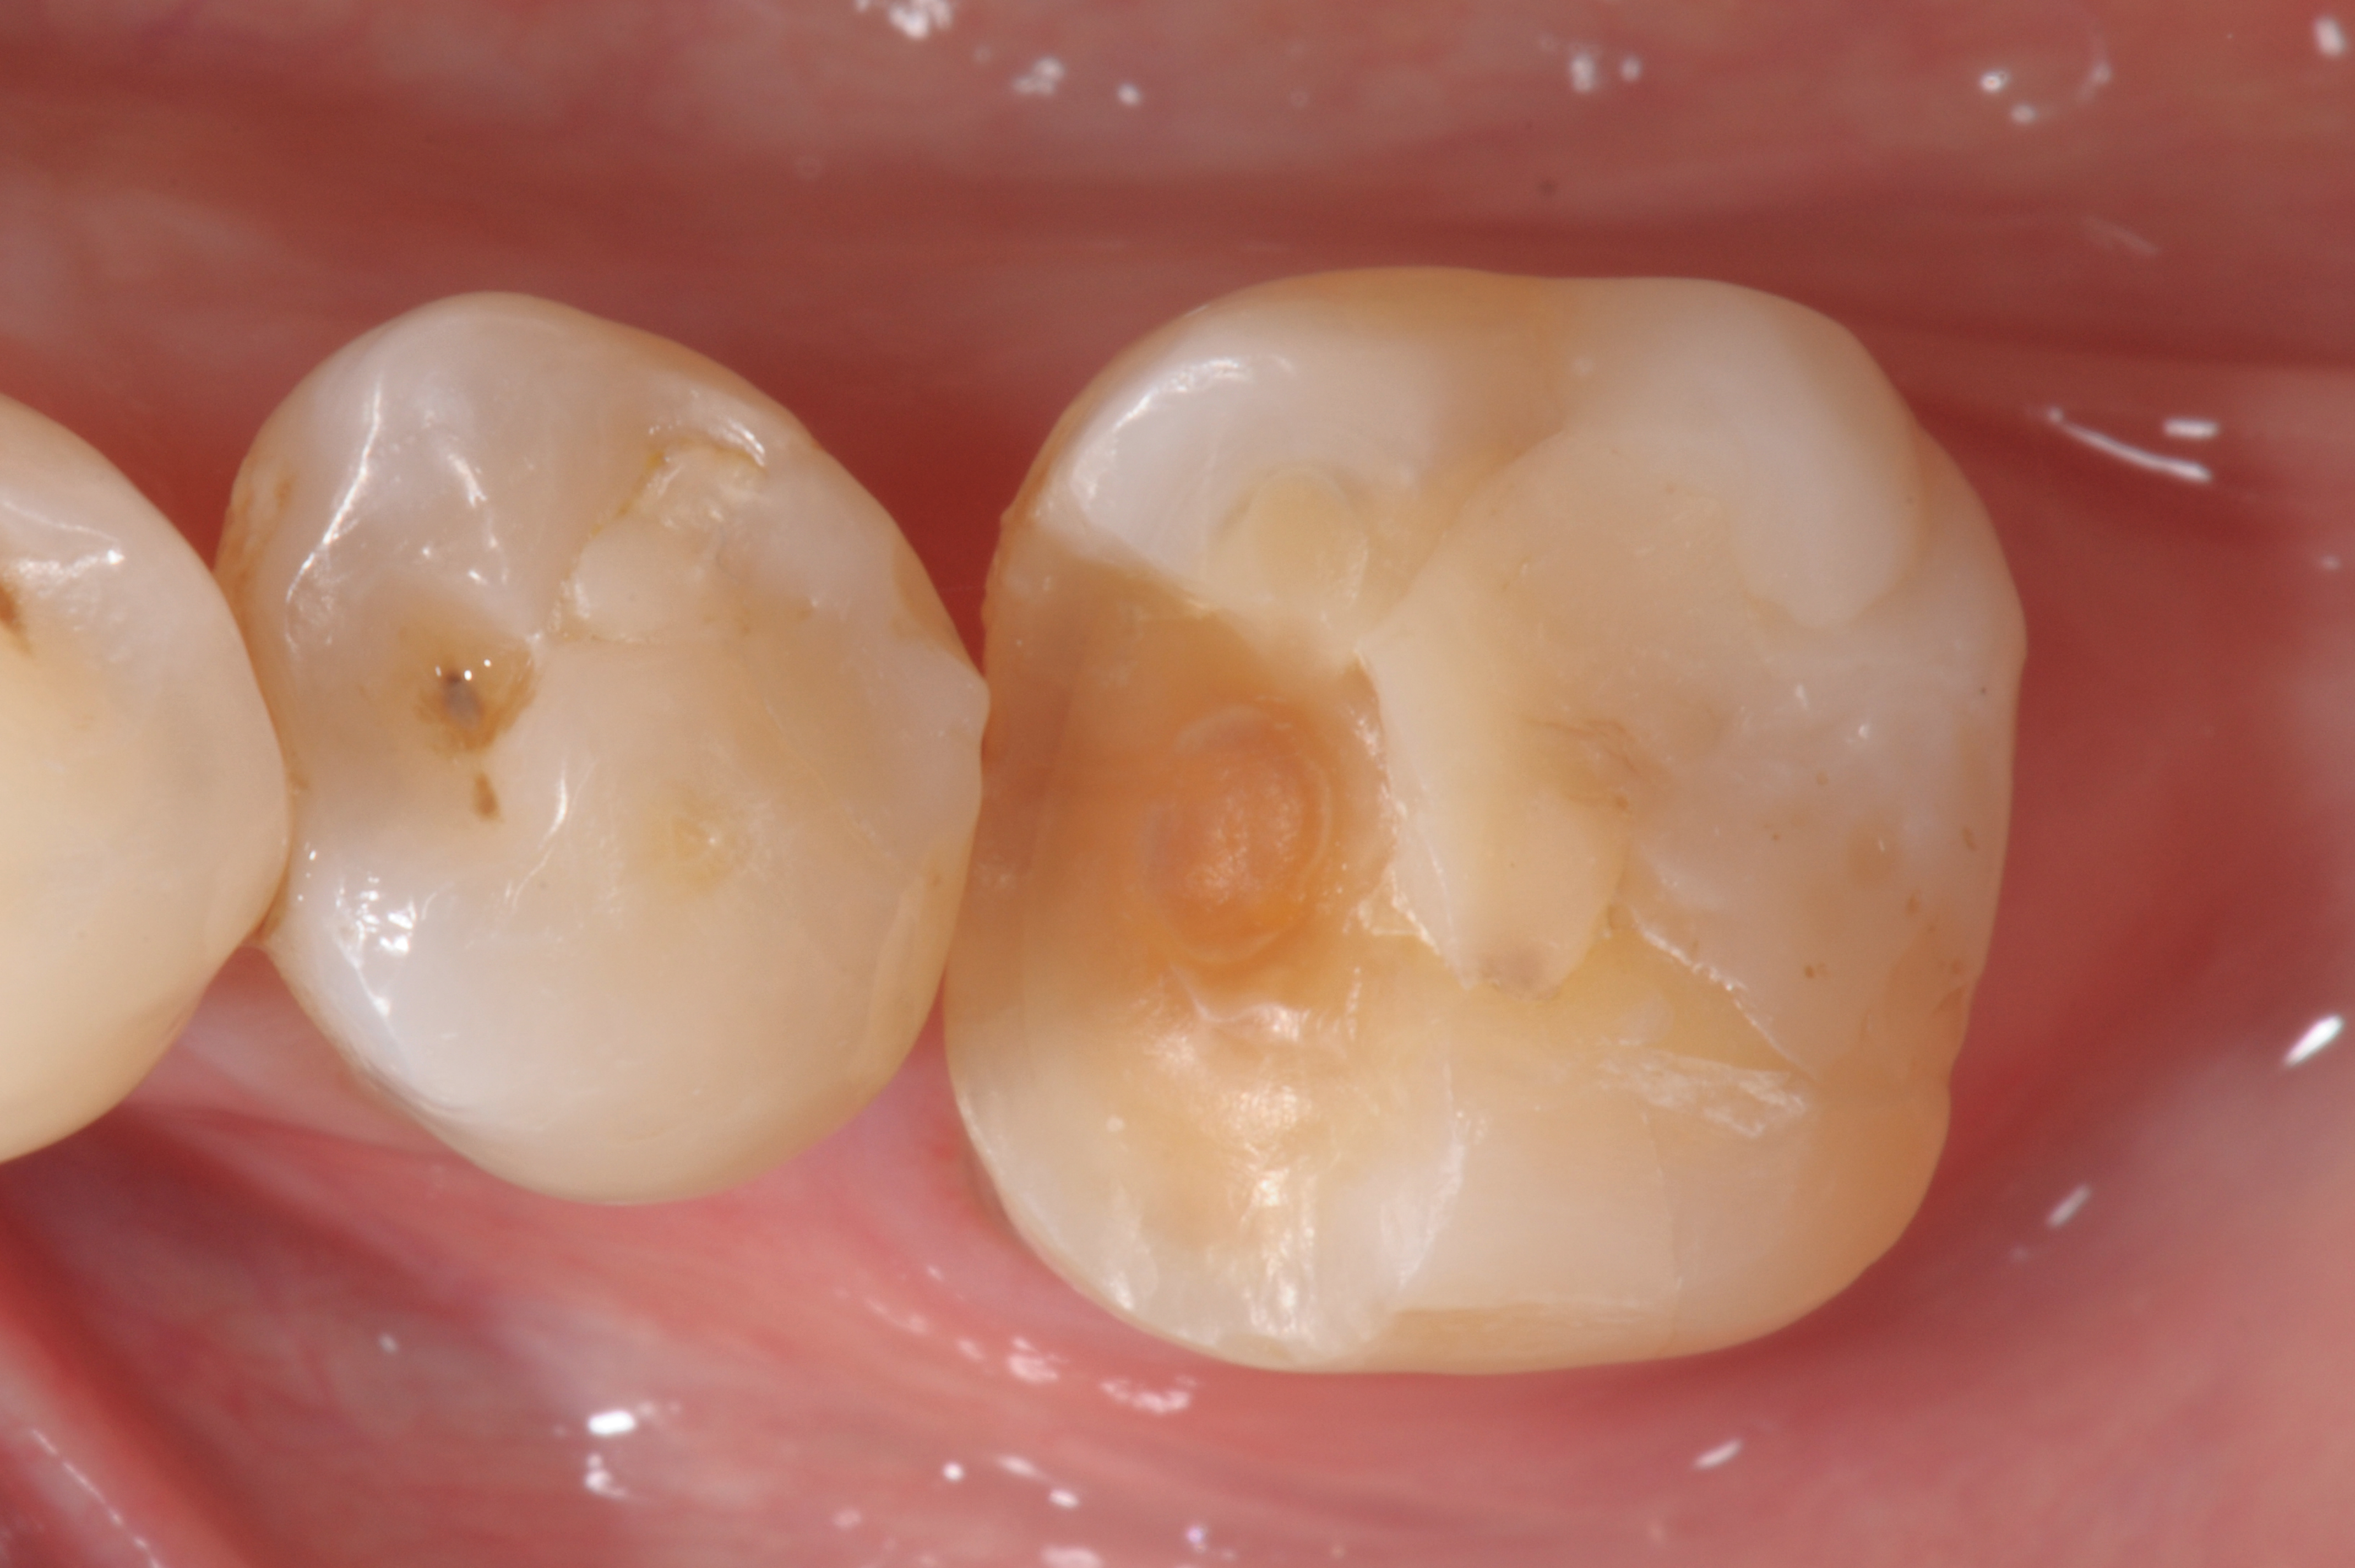

When following a protocol of cementation using an adhesive system, constant rubber dam isolation and careful hand finishing are necessary to provide predictable clinical results (Figure 1 through Figure 4).2

Fig 3. Cementation of an indirect composite restoration.

Figure 3

Fig 4. Postoperative view.

Figure 4